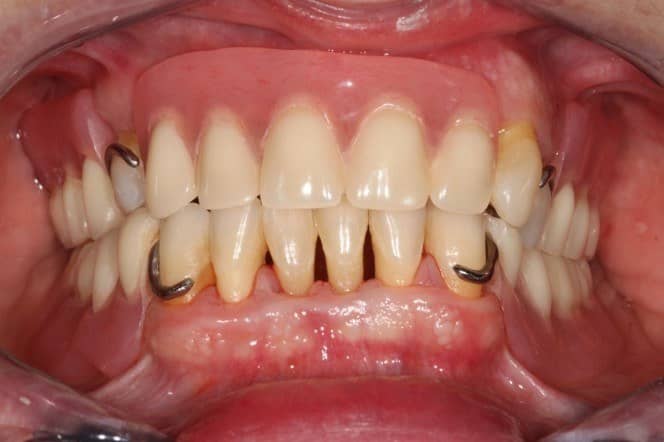

6

Ezek az öntött kapcsok a pótlás viselésekor sajnos nem túl esztétikusak, ám van, amikor eme hátrány ellenére is ez a fogpótlás jelenti a megoldást. Páciensünk mindenesetre maradéktalanul elégedett volt megújult mosolyával!

Kapcsos részleges lemezes fogpótlás után